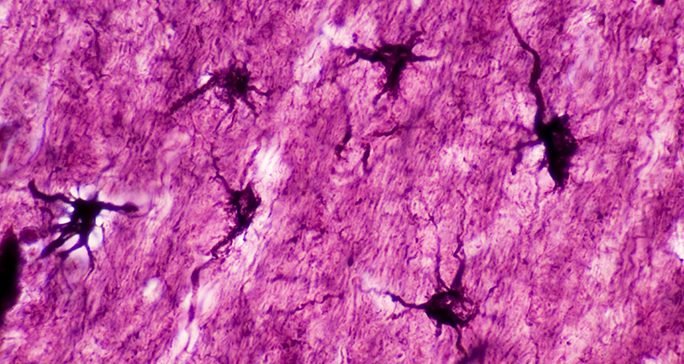

Gliomas develop from glial cells, which support neurons and perform other essential roles in the brain.

Astrocytoma: Astrocytomas are also cancerous tumors. They develop from astrocytes, which provide nourishment to neurons in the brain. They are diagnosed as grade 2, 3 or 4.